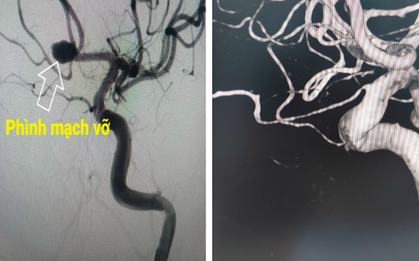

Phình động mạch não là tình trạng phình ra ở vùng động mạch não bị suy yếu. Khi có các yếu tố thuận lợi thì sẽ có một lượng máu lớn dồn về chỗ phình và nhiều khả năng gây vỡ mạch máu, gây ra tình trạng xuất huyết (chảy máu) trong não và đe dọa tính mạng người bệnh.